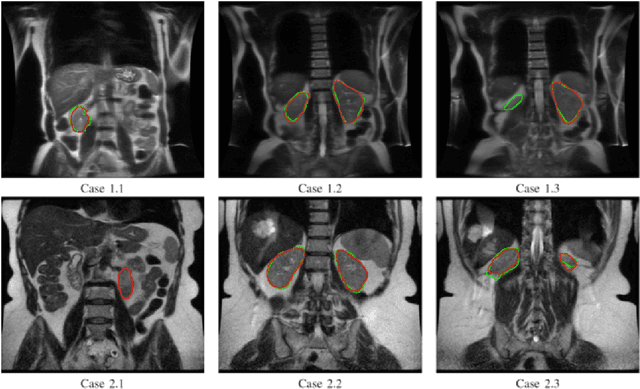

Abstract:Despite the recent advances of deep learning algorithms in medical imaging, the automatic segmentation algorithms for kidneys in MRI exams are still scarce. Automated segmentation of kidneys in Magnetic Resonance Imaging (MRI) exams are important for enabling radiomics and machine learning analysis of renal disease. In this work, we propose to use the popular Mask R-CNN for the automatic segmentation of kidneys in coronal T2-weighted Fast Spin Eco slices of 100 MRI exams. We propose the morphological operations as post-processing to further improve the performance of Mask R-CNN for this task. With 5-fold cross-validation data, the proposed Mask R-CNN is trained and validated on 70 and 10 MRI exams and then evaluated on the remaining 20 exams in each fold. Our proposed method achieved a dice score of 0.904 and IoU of 0.822.